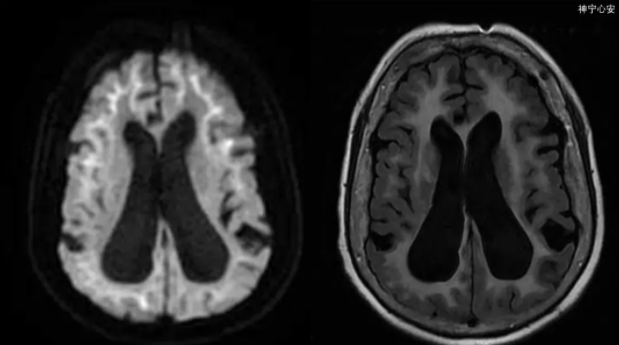

发病率仅次于阿尔茨海默病!一次中风,变得判若两人......

七旬老太记忆不好竟不是老年痴呆!杭七院MDT团队剥丝抽茧最终确诊罕见病